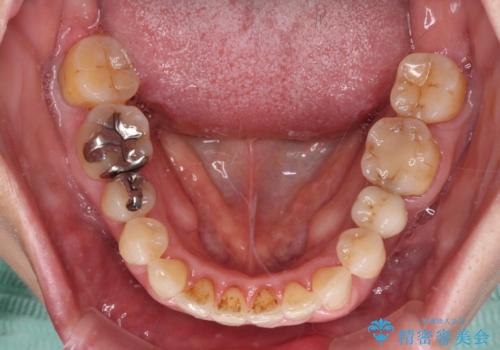

- 近医にてインプラント治療を行った後に矯正治療を希望され、来院された患者様です。

口元の突出感とデコボコが気になっているとのことでしたが、インプラントが既に3本埋入されていたため、抜歯矯正による口元を引っ込めることができない状況でした。

近医での歯周病治療の影響でブラックトライアングルが発現していたため、IPR(歯と歯の間を削る)で隙間を改善しつつ、インプラントを固定源に歯列全体を後方へ移動させることとしました。